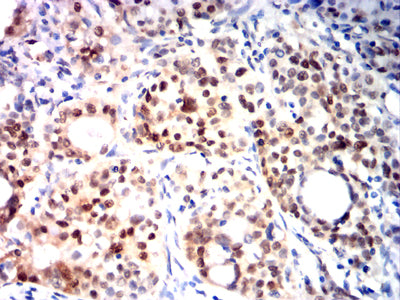

Immunohistochemical analysis of paraffin-embedded human cervical cancer tissues using KMT2A mouse mAb with DAB staining.